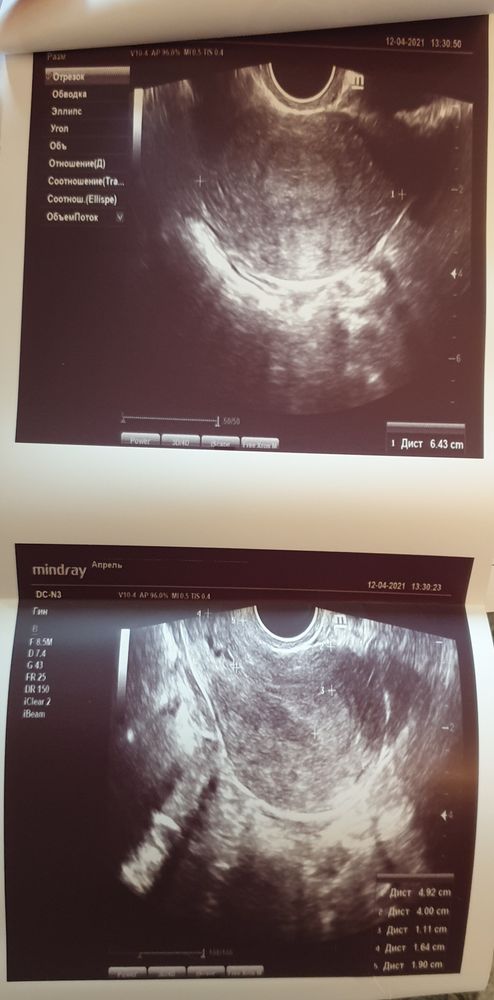

Добрый день, девочки) У меня в этом цикле опять большая задержка, пошла делать узи в платную клинику. Узи какое-то смазанное впечатление оставило, делала не больше 1,5 минут. Врач сказала, что эндометрий пышный, что у нее ощущение, что должны скоро пойти месячные. Я спросила, значит была овуляция, она ответила, что не знает, т.к. нет свободной жидкости. Девочки, разве может быть эндометрий 11 мм без овуляции? Про желтое тело спросить не сообразила, может оно уже угасло? Мне это важно, т.к. я считала длинные циклы ановуляторными. Все звала меня к себе на консультацию, как к гинекологу-эндокринологу. Написала аденомиоз под вопросом, в целом сказала, что ничего страшного нет по узи. Вы бы пошли к такому врачу наконсультацию?

У вас яичники без жт и не увеличены. Всё таки если было/есть жт яичник по размеру был бы больше